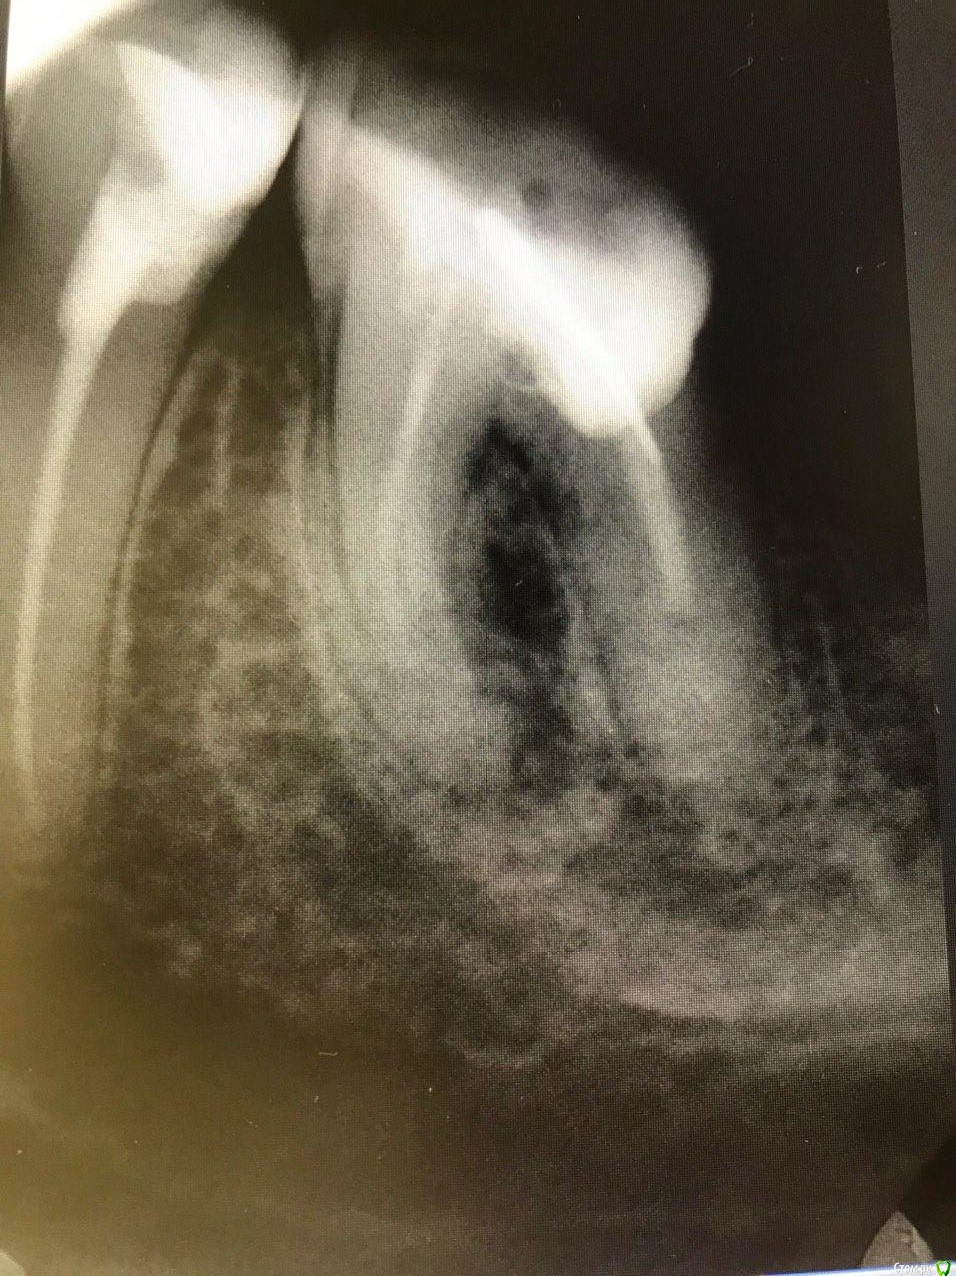

1586Doc Опубликовано 8 февраля, 2020 Поделиться Опубликовано 8 февраля, 2020 5 месяцев назад обратилась пациентка с симптоматикой периодонтита. Оценили, попробовали. Пломбировка вертикалка. 5 месяцев и контроль, боли нет, подвижности тоже. 2 Ссылка на комментарий

1586Doc Опубликовано 10 февраля, 2020 Автор Поделиться Опубликовано 10 февраля, 2020 (изменено) А где контроль на сегодня? При таком качестве снимков оценить будет тяжело.первые 2 фото снимки 9 месяц назад, до ревизии Изменено 10 февраля, 2020 пользователем 1586Doc Ссылка на комментарий